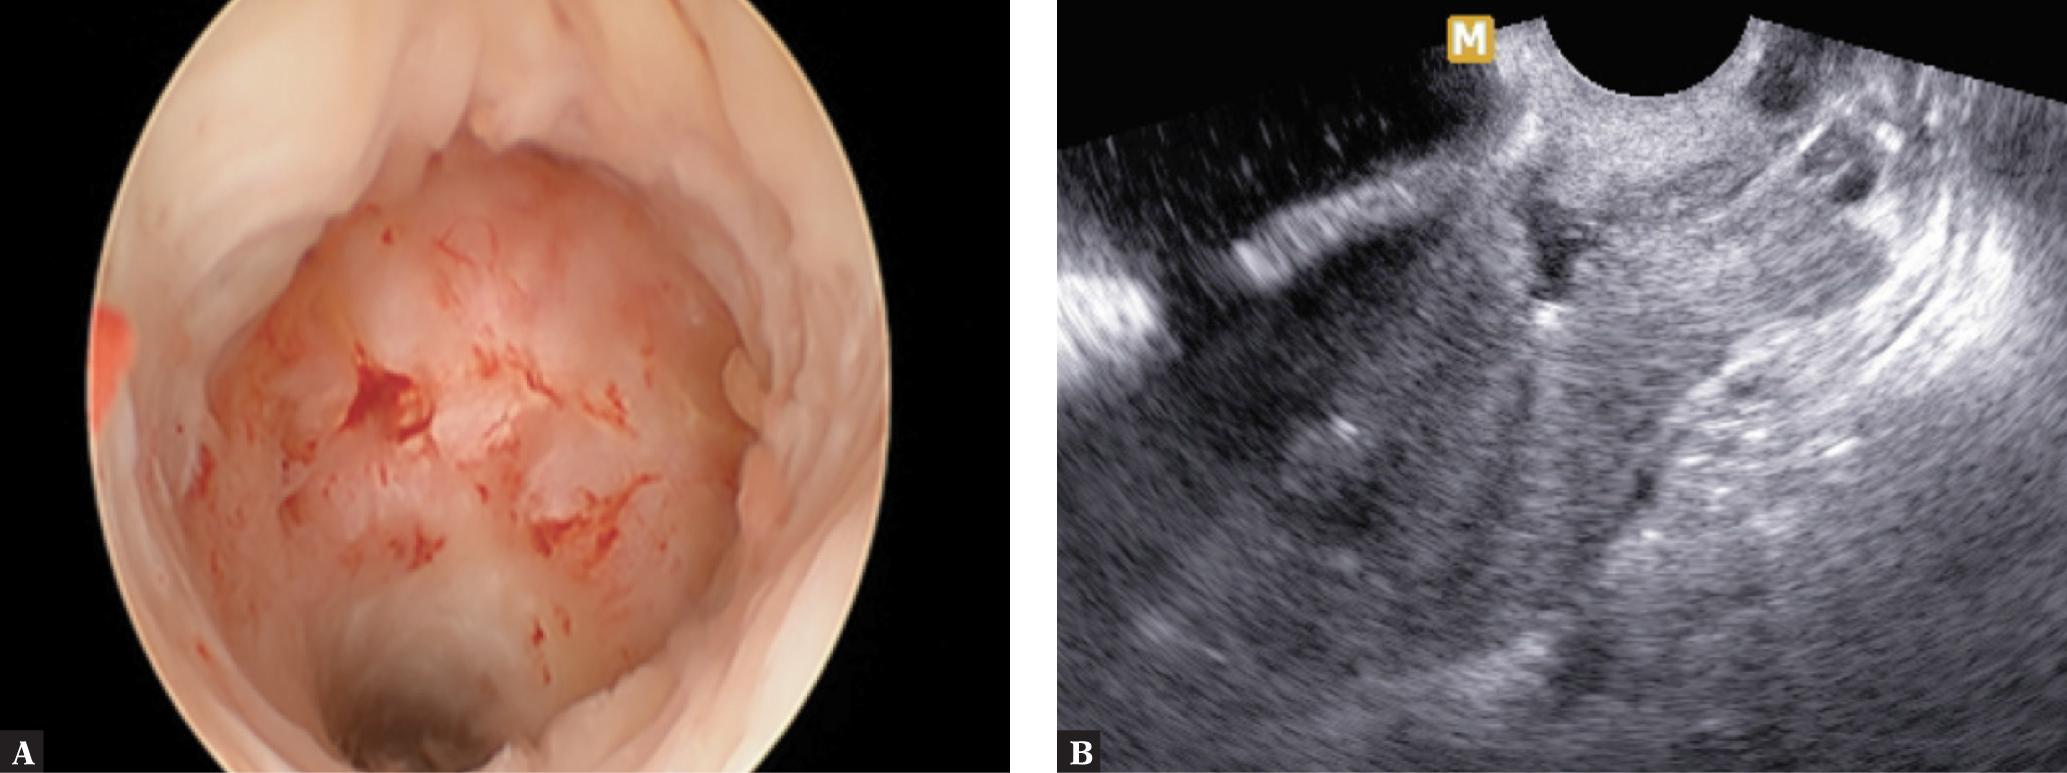

The differential diagnosis for CSEP must include spontaneous miscarriage, missed miscarriage and cervical EP. The diagnosis of a CSEP is invariably challenging, as approximately 30% of patients may not present with any symptoms, and in 70% the symptoms mimic EP. TVS is the most accurate differential test, with a sensitivity of 84.6%. Additionally, saline infusion sonohysterography, MR, 3D US and hysteroscopy may also be helpful(5) (Fig. 1).

A. A CS scar defect visible in a hysteroscopic evaluation. B. CS scar defect (niche) visible in a US evaluation